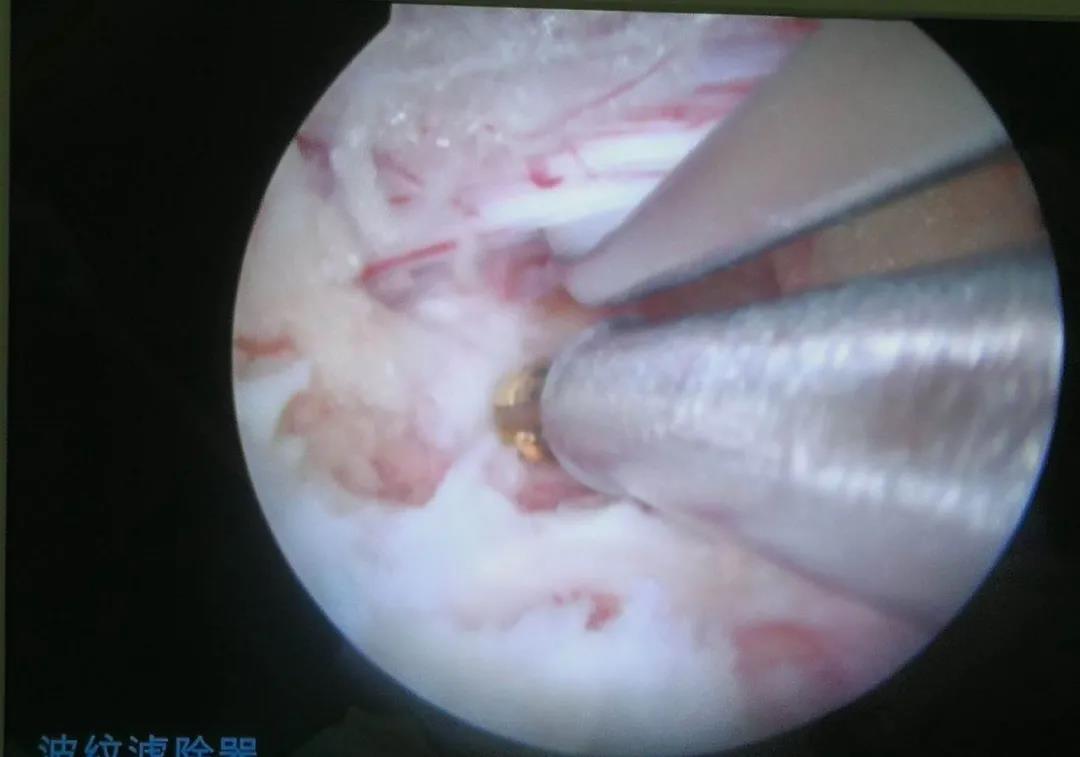

保護(hù)拉鉤牽開神經(jīng)根暴露突出鈣化的椎間盤

髓核鉗清除突出鈣化的椎間盤